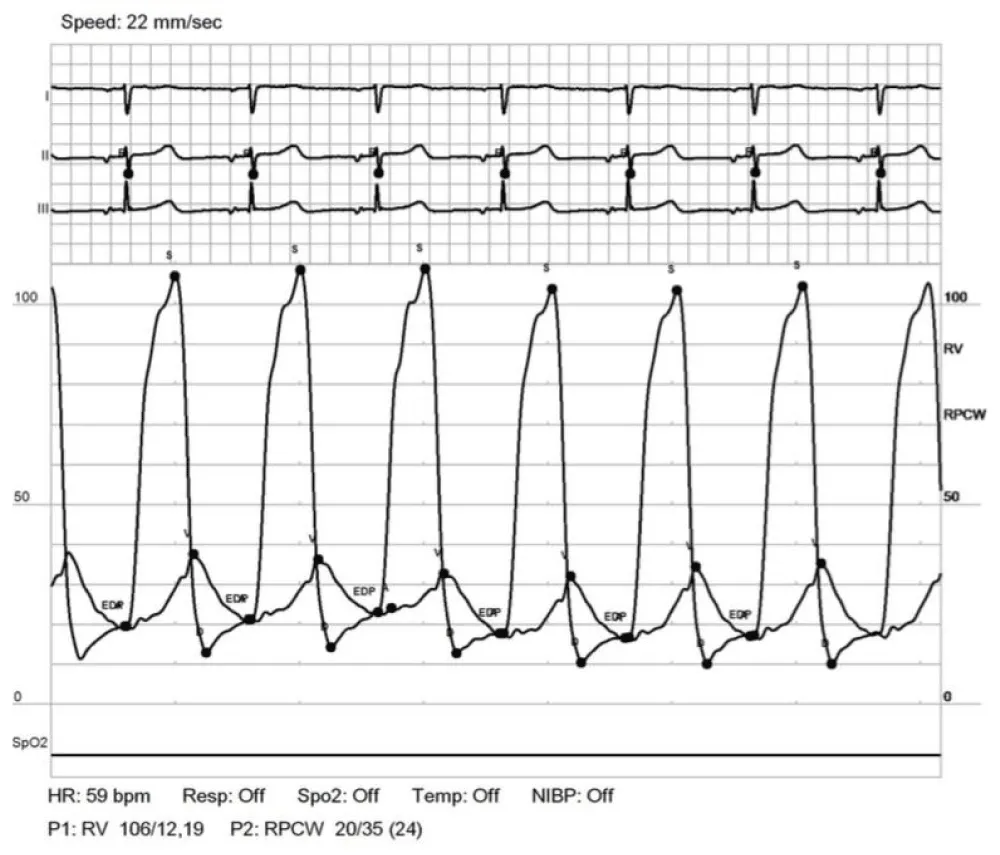

Patient 2 is a 34-year-old woman with a history of D-TGA palliated with a Rashkind atrial septostomy as a neonate and eventually a Mustard procedure (atrial-switch operation with dacron-constructed baffles) at the age of 11 months. Due to obstruction of the systemic venous baffle, she underwent a baffle reconstruction with Gore-tex material at the age of 7 years. She was monitored for long-standing (> 20 years) mild pulmonary venous baffle obstruction (mean 4-5 mmHg gradient across the baffle by serial echo) without significant pulmonary hypertension. Serial echocardiograms noted that the pulmonary venous baffle was diffusely “echo bright” and was presumed secondary to calcification. The gradient across the pulmonary venous baffle did worsen (to mean 9-15 mmHg) during her two successful pregnancies, requiring peripartum diuresis. After each delivery gradients returned to baseline and diuretics were discontinued. At the age of 32 years (4 years postpartum), she developed slowly progressive, severe exercise intolerance and a feeling of chest heaviness. Echocardiogram at that time demonstrated Mustard anatomy, low/normal RV function, mild tricuspid regurgitation, and the known diffusely calcified pulmonary venous baffle with mean pressure gradient of 4-6 mmHg and peak of 22 mmHg through the baffle. Cardiac catheterization (Table 2) demonstrated mild pulmonary hypertension with mean pulmonary artery pressure of 32 mmHg and, as with patient 1, markedly elevated V waves on pulmonary artery wedge tracings. PCWP A waves were measured at 20 mmHg and commensurate with the RVEDP of 19 mmHg; V waves were 35 mmHg (Figure 2).

Figure 2: Simultaneous RV and PCWP tracing for patient 2. Tracings demonstrate A wave pressure that correlates with RVEDP and a very large V wave.

We describe two patients with diffuse and heavy pulmonary venous baffle calcification resulting in a stiff, non-compliant neo-left atrium and pulmonary hypertension greater than 30 years post-Mustard procedure for D-TGA. In patient 1, we describe the phenomenon from a hemodynamic standpoint (mixed arteriolar and non-arteriolar pulmonary hypertension with very large baffle V waves and no discrete obstruction across the baffle), as well as cardiac-gated CT confirmation (heavily calcified, non-compliant baffle that moves en bloc with the beating ventricle). In patient 2, we re-demonstrate the hemodynamic characteristics of this phenomenon, and though her surgery was ultimately undertaken due to a complication of cardiac catheterization, the revision of her pulmonary venous baffle with neo-left atrial enlargement and subsequent complete resolution of symptoms, serves as proof-of-concept that this degree of chamber non-compliance is causative of severe symptomatology and surgery can be curative. We believe that without baffle enlargement that patient 2 would have suffered continued symptoms similar to those prior to their catheterization.